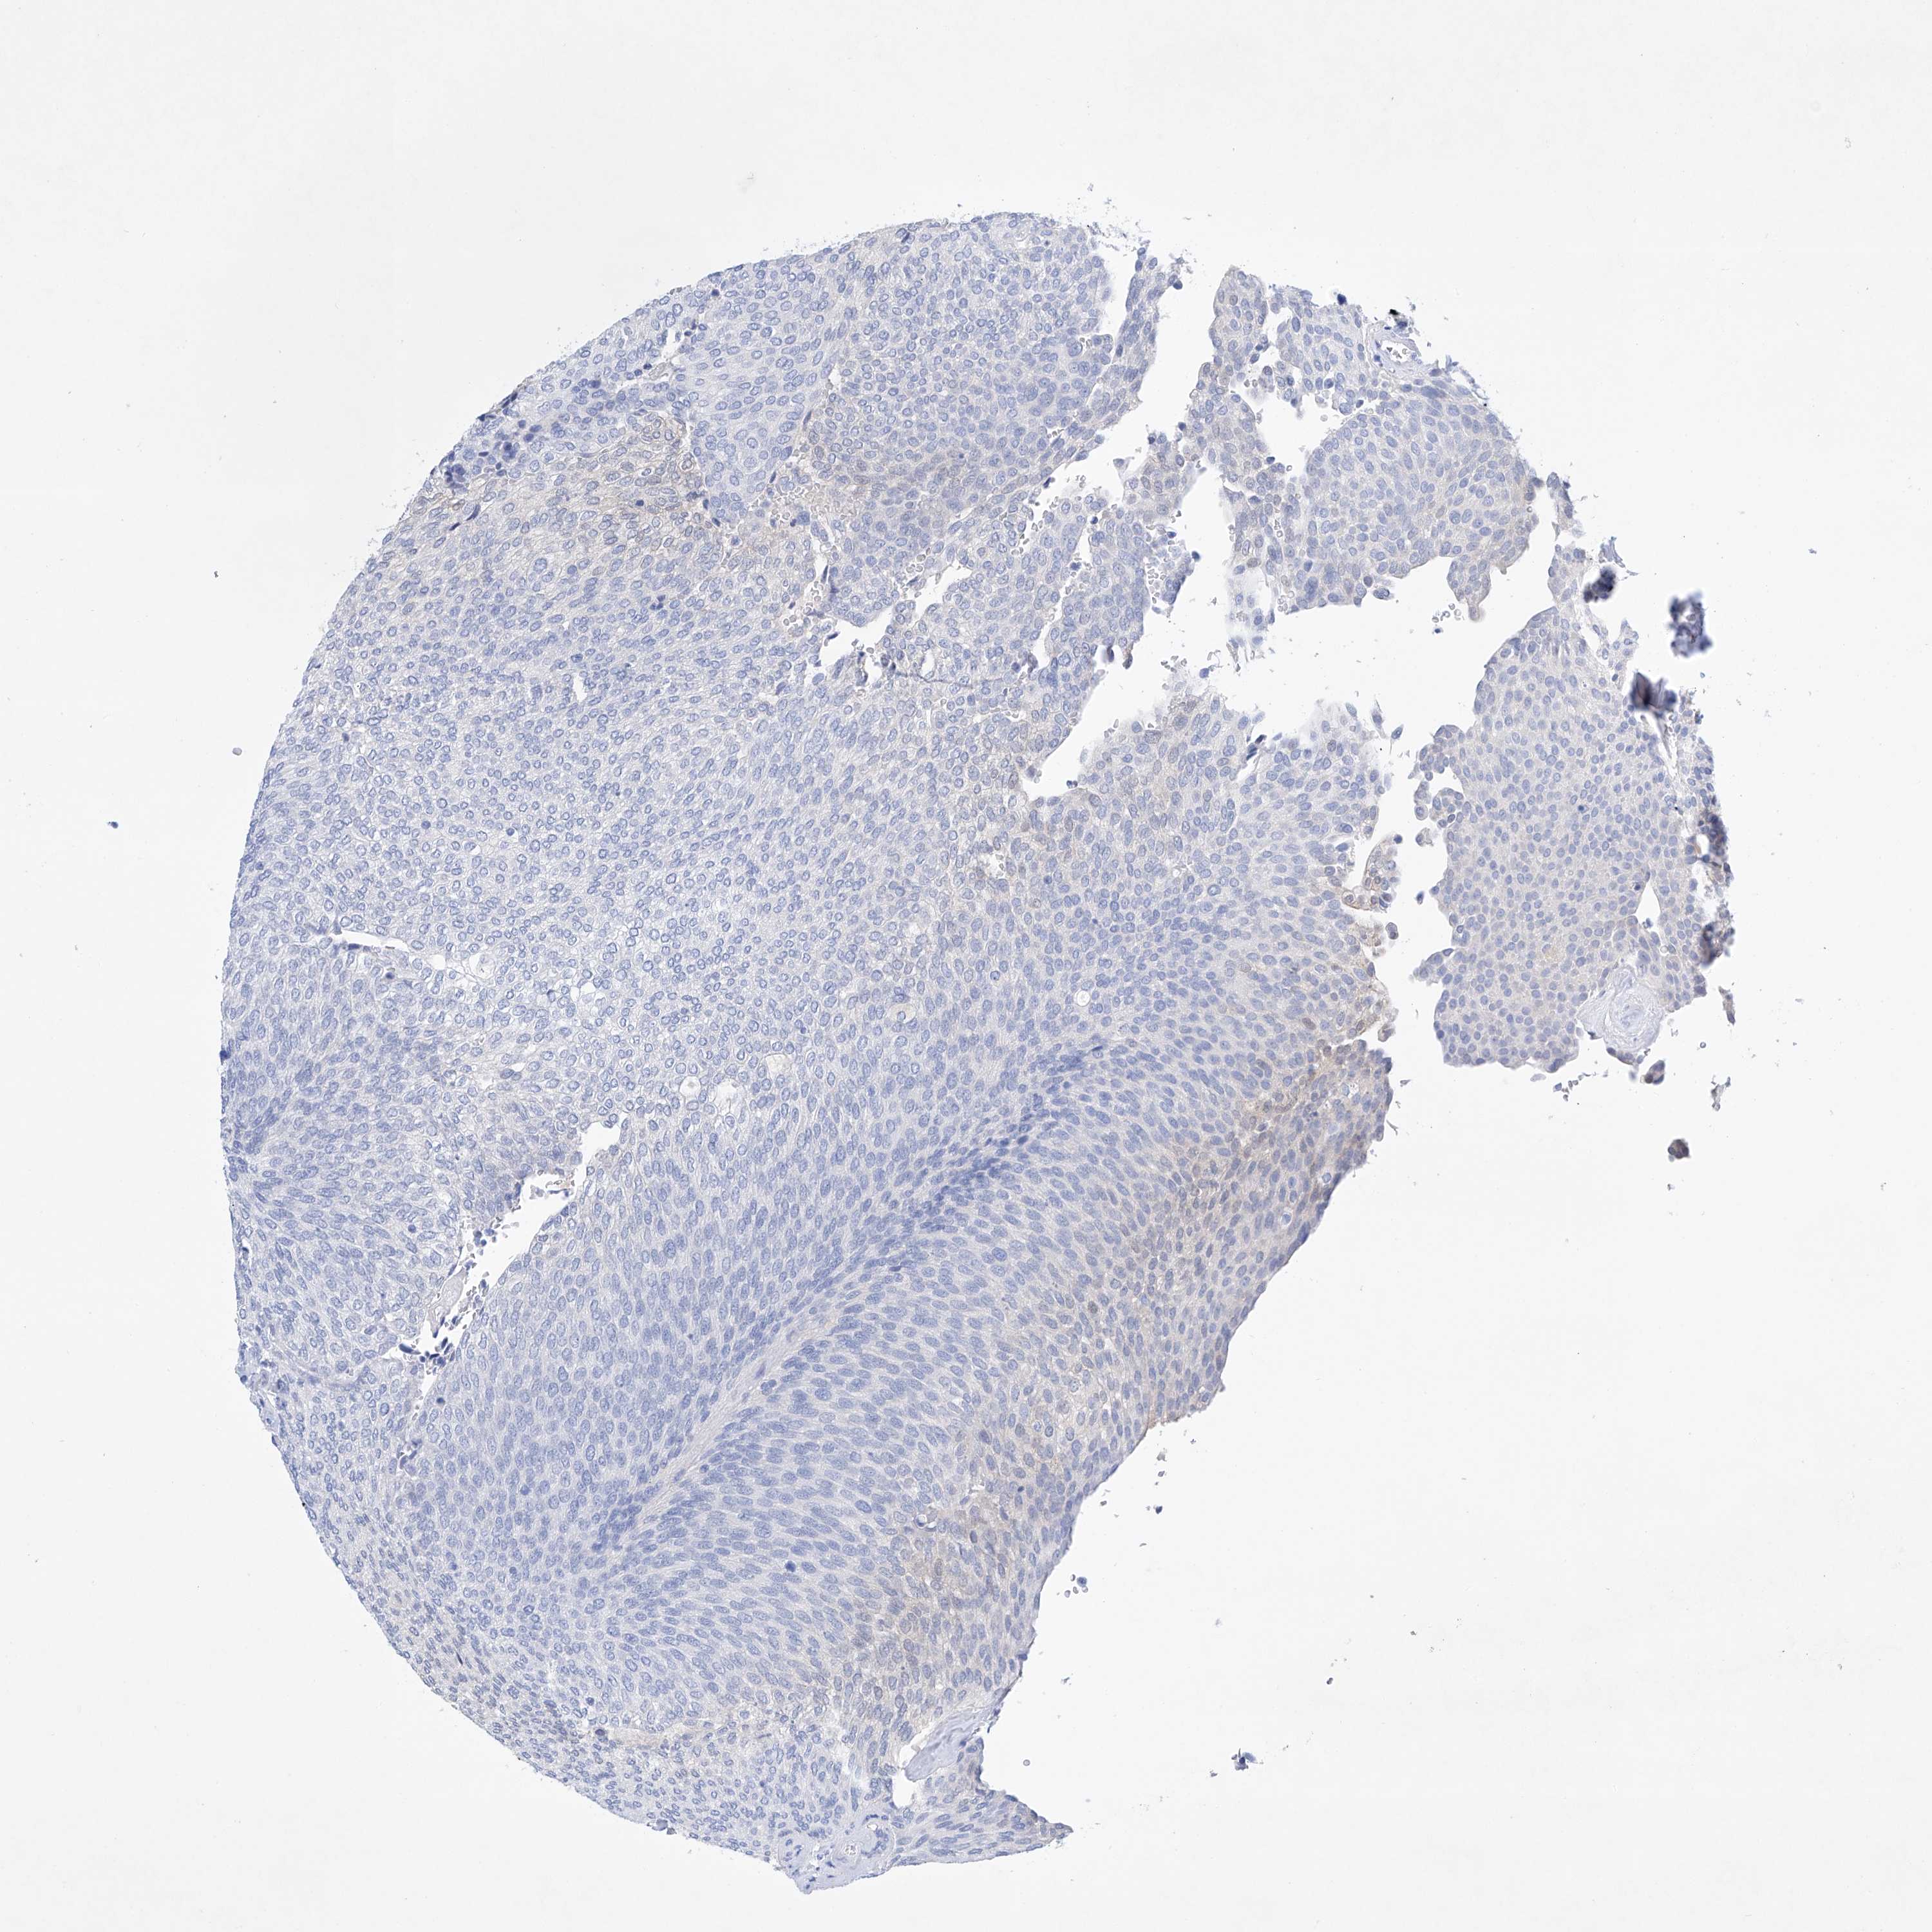

UROTHELIAL CANCER - Protein expressioni

A mouse-over function shows sample information and annotation data. Click on an image to view it in a full screen mode. Samples can be filtered based on level of antibody staining by selecting one or several of the following categories: high, medium, low and not detected. The assay and annotation is described here.

Note that samples used for immunohistochemistry by the Human Protein Atlas do not correspond to samples in the TCGA dataset.

Antibody stainingi

Antibody staining in the annotated cell types in the current human tissue is reported as not detected, low, medium, or high, based on conventional immunohistochemistry profiling in selected tissues. This score is based on the combination of the staining intensity and fraction of stained cells.

Each image is clickable and will lead to virtual microscopy that enables deeper exploration of all samples and also displays staining intensity scores, fraction scores and subcellular localization as well as patient and tissue information for each sample.

Antibody HPA030060

Antibody HPA030061

Urothelial carcinoma, Low grade